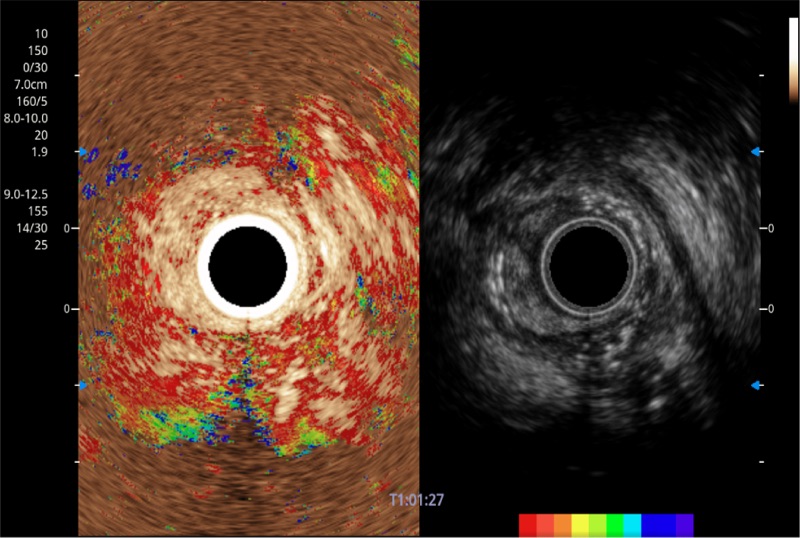

可人为将灰阶图像转变成彩色的显示方式,增强人眼对于不同回声强度的敏感度,主观上增加了图像分辨率

微米成像技术提升了对组织斑点噪声信号的抑制能力,并进一步强化边界信息,从而获得信噪比更优、边界更清楚锐利的图像

食管内间质瘤清晰显像

清晰显示胆总管及周围血管分布

肝左叶和肝静脉的横截面